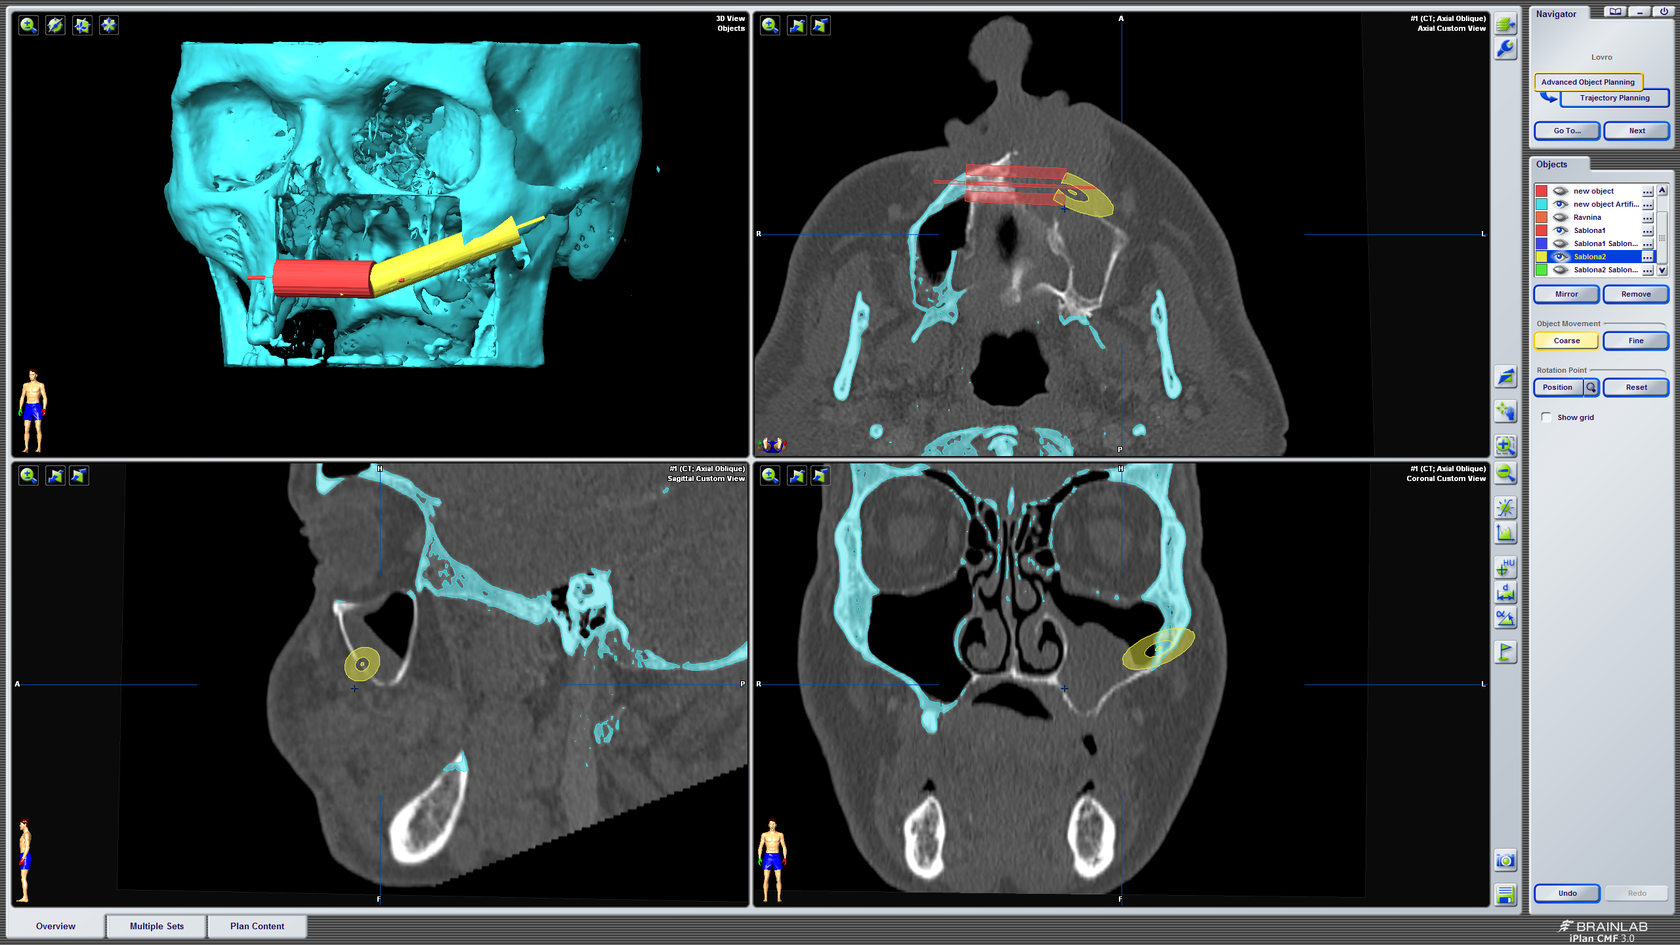

3D kompjutorsko planiranje rekonstrukcije defekta gornje čeljusti